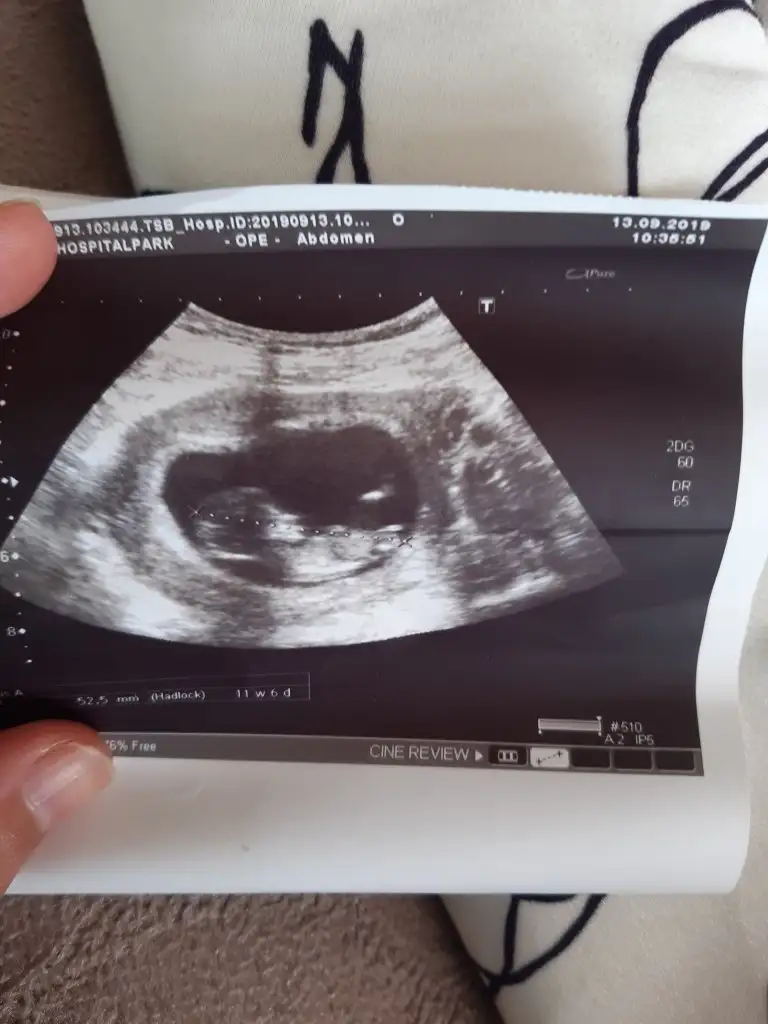

Arkadaşlar bebegimin cinsiyetine bakar mısınız 11+6 haftalık 9. Haftalıkken atmıştım ama net değildi şimdi atmak istedim